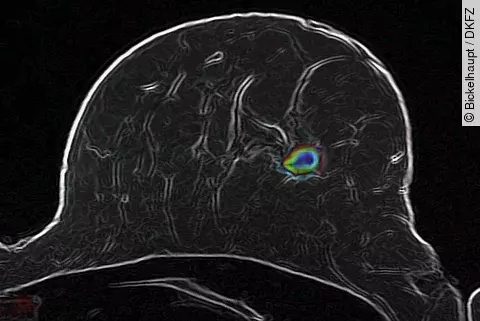

HirntumorenKünstliche Intelligenz hilft, Therapieansprechen besser zu beurteilen

Ein Team vom Universitätsklinikum Heidelberg (UKHD) und vom Deutschen Krebsforschungszentrum (DKFZ) hat ein neues Verfahren zur automatisierten Bild-Analyse von Hirntumoren entwickelt. In ihrer aktuellen Arbeit zeigen die Autoren, dass anhand von Standard-Magnetresonanztomographien (MRT) sorgfältig trainierte maschinelle Lernverfahren das…